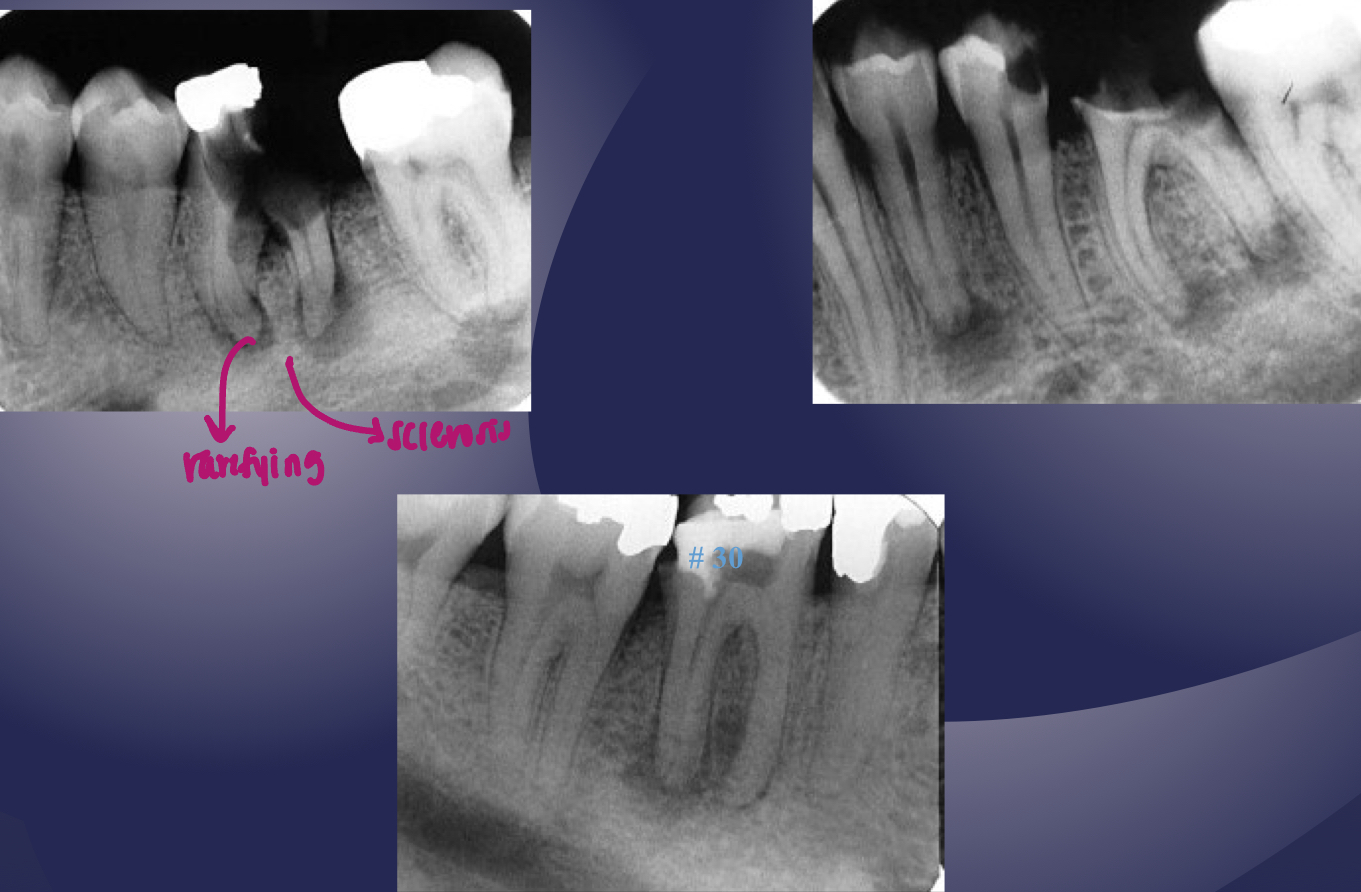

rarefying osteitis

rarefying osteitis (LD gone and radiolucency)

chronic inflam with a non-vital toothÂ

radiolucent due to removal of bone

hardening of the bone; bone deposition increase in radiopacity of bone (plus widened PDL)

sclerosing osteitisÂ

sclerosing osteitis

bone deposition around area of rarefaction

sclerosing osteitis + radiolucency